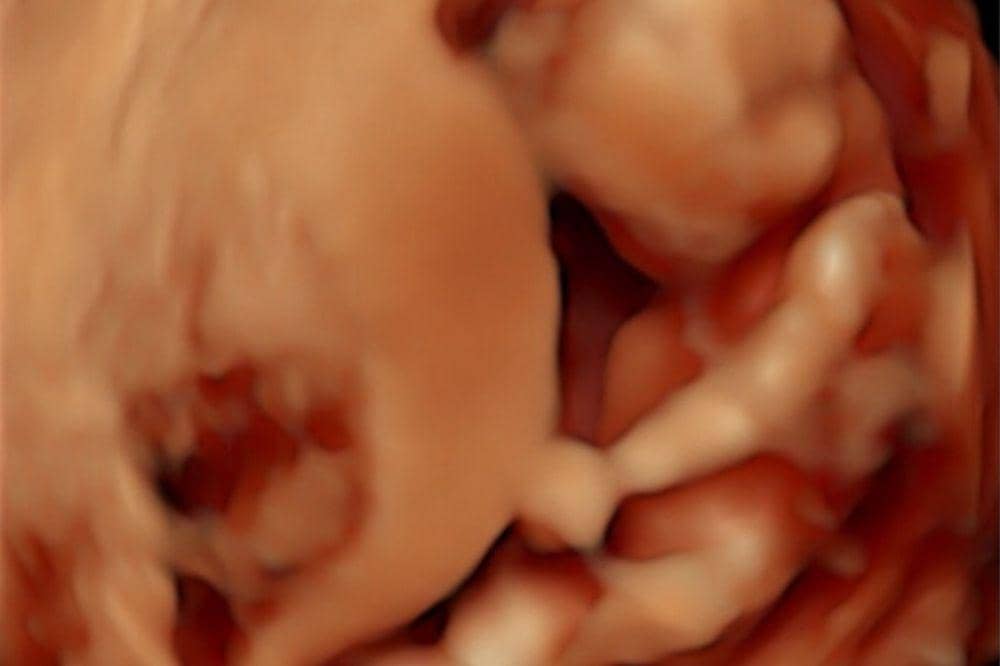

2. Rigen membagikan potret USG calon anak keempat

Selain foto keluarga, Rigen juga memperlihatkan hasil USG kehamilan Indah dalam unggahannya. Sayangnya, mereka tidak menjelaskan lebih lanjut mulai dari usia kehamilan dan sebagainya.

Dari tampilan USG 3D yang dibagikan, janin dalam perut Indah sudah terlihat cukup terbentuk jelas di mana kepala, wajah, badan, serta bakal lengan dan tangan sudah bisa dibedakan. Berdasarkan ciri visualnya ini kemungkinan besar berada di trimester pertama akhir menuju awal trimester kedua, sekitar usia kehamilan 11–14 minggu.